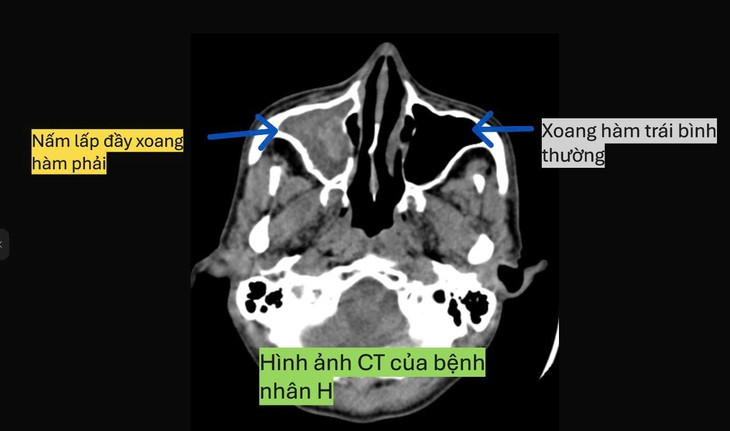

Sau khi tiến hành nội soi tai mũi họng và chụp phim cắt lớp vi tính mũi xoang, Bs. Ngọc Văn Sinh, Khoa Răng hàm mặt- Mắt- tai mũi họng, phát hiện anh H. có ổ nấm xoang hàm phải, lập tức chỉ định phẫu thuật nội soi lấy sạch tổ chức nấm mủn đen và mở rộng lỗ thông xoang.

Quá trình phẫu thuật, bệnh nhân được BS. Ngọc Văn Sinh bảo tồn tối đa niêm mạc lành, không tổn thương ống lệ tị, nhánh động mạch bướm khẩu cái và được bơm rửa sạch hốc mổ, tránh tồn dư tổ chức nấm làm bệnh tái phát.

Sau 3 ngày phẫu thuật, bệnh nhân H không còn chảy mũi hay thấy khó chịu, mùi hôi trong mũi, đỡ đau nhức vùng mặt, mũi thông thoáng.